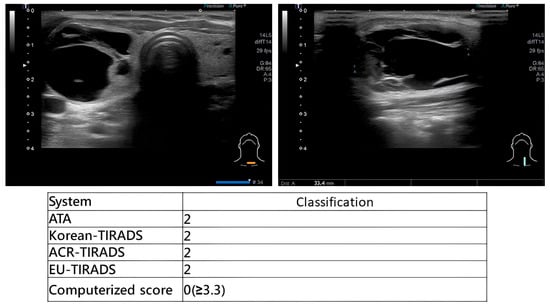

Comparative Diagnostic Performance of Ultrasound-Based Risk Stratification Systems in Thyroid Nodule Evaluations by Otolaryngologists

Background/Objectives: Thyroid nodules are a prevalent condition with a high incidence rate of malignancy. Ultrasound (US)-based risk stratification systems have become widely utilized for the evaluation of thyroid nodules, including the American Thyroid Association (ATA) guidelines, the American College of Radiology Thyroid Imaging [...] Read more.

Background/Objectives: Thyroid nodules are a prevalent condition with a high incidence rate of malignancy. Ultrasound (US)-based risk stratification systems have become widely utilized for the evaluation of thyroid nodules, including the American Thyroid Association (ATA) guidelines, the American College of Radiology Thyroid Imaging Reporting and Data System (ACR-TIRADS), the Korean Society of Thyroid Radiology system (K-TIRADS), and the European Thyroid Association system (EU-TIRADS). Our institution has developed a real-time computerized score for evaluating thyroid nodules. This study aims to systematically compare the diagnostic performance of these systems when applied in real time by otolaryngologists, who integrate dynamic US imaging with physical examination. Methods: Patients with thyroid nodules who underwent US evaluation, US-guided fine-needle aspiration cytology (FNAC), and subsequent thyroidectomy were included. During each examination, otolaryngologists performed real-time risk categorization according to five US-based systems, with immediate scoring based on dynamic sonographic findings. Results: From April 2021 to November 2023, 130 patients were enrolled. For categories 4 and 5, the ATA guidelines had a sensitivity of 96.6% (95% CI: 87.3–100%), specificity of 78.9%, (60.6–97.3%) PPV of 84.6% (70.7–98.5%), NPV of 93.7% (81.9–100%), and accuracy of 88.1% (78.3–97.9%). The sensitivity of the ACR-TIRADS was 95.6% (87.3–100%), the specificity was 78.9% (60.6–97.3%), the PPV was 84.6% (70.7–98.5%), the NPV was 93.7% (81.9–100%), and the accuracy was 88.1% (78.3–97.9%). Both the K-TIRADS and the EU-TIRADS had sensitivities of 95.6% (87.3–100%), specificities of 78.9% (60.6–97.3%), PPVs of 84.6% (70.7–98.5%), NPVs of 93.7% (81.9–100%), and accuracies of 88.1% (78.3–97.9%). The computerized score (>3.3 considered malignant) and TBSRTC (Category 5 or 6) both had sensitivities of 73.9% (56.0–91.9%), specificities of 100%, PPVs of 100%, NPVs of 76.0% (59.3–92.7%), and accuracies of 85.7% (75.1–96.3%). Conclusions: Otolaryngologists can achieve highly accurate diagnostic performance when applying standardized ultrasound-based risk stratification systems, and a real-time computerized scoring system provides highly specific supplemental value for immediate clinical decision-making. Full article

Show Figures

Figure 1